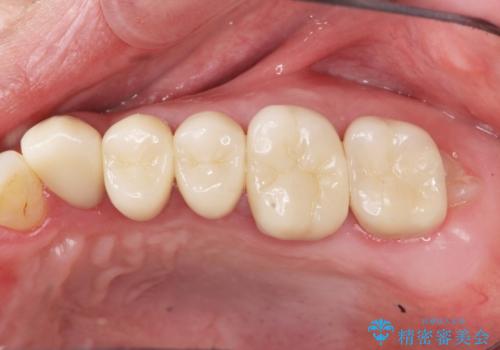

- 92.4万円(ジルコニアクラウン×7・仮歯×7)費用は治療当時の料金となります

適合の良いセラミック治療をおこなったことで、歯ブラシがしやすくなり銀歯の見た目だけでなく歯ぐきの状態も大幅に改善することができました。